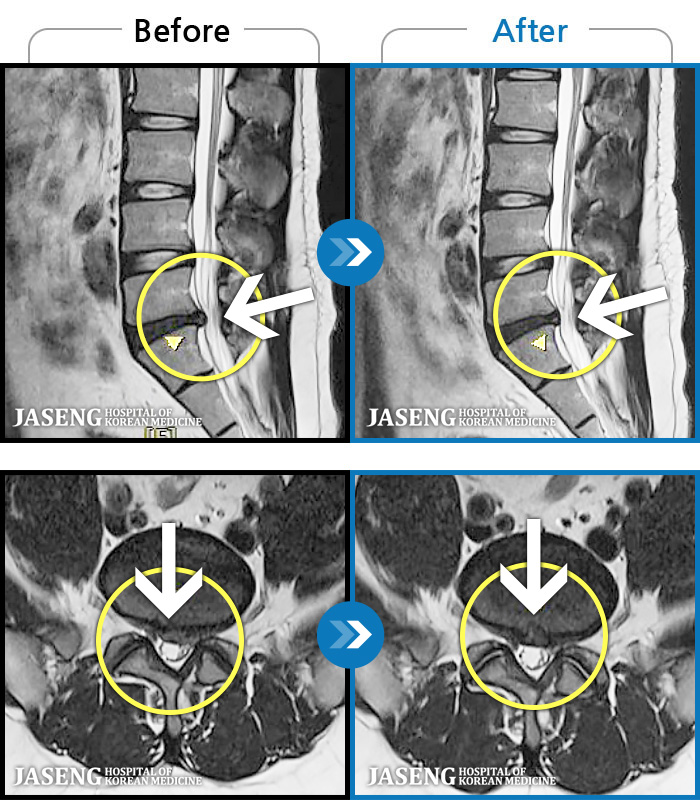

Before

After

양측 허리 묵직하고 뻐근한 통증, 우측 다리까지 이어지는 저림 증상 및 통증으로 내원하셨습니다.

2025.01.21 ~ 2025.11.18